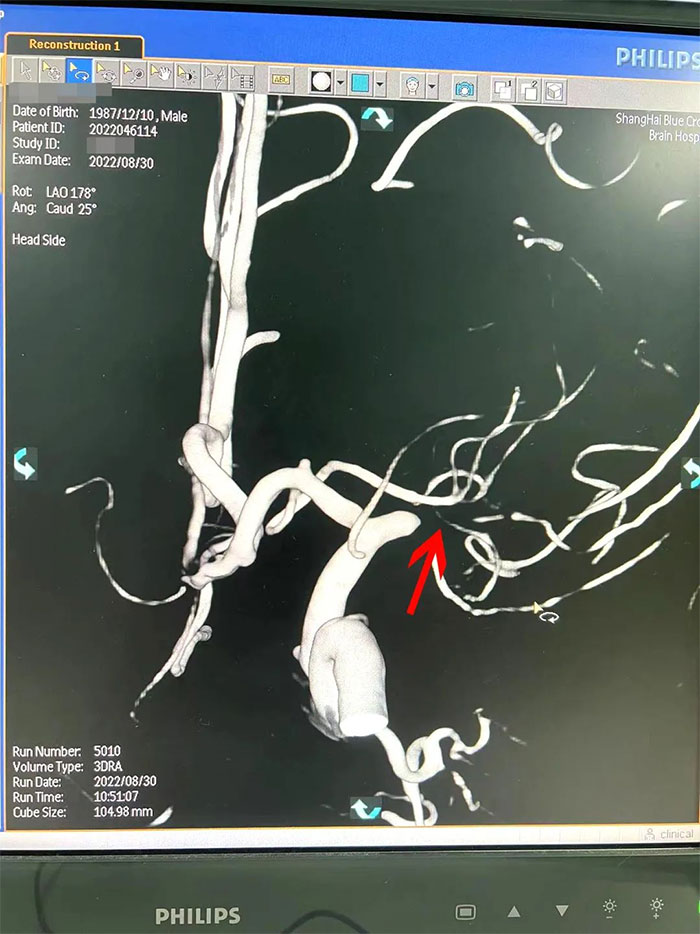

在與患者及家屬充分溝通后,李振并主任為周先生展開了DSA(數(shù)字減影血管造影)檢查。

在檢查中發(fā)現(xiàn),周先生右側(cè)大腦中動脈M1段閉塞,可見煙霧狀異常血管網(wǎng)生成;左側(cè)大腦中動脈M1段重度狹窄(約70%)。符合煙霧病的典型影像學(xué)特征。

▲右側(cè)大腦中動脈M1段閉塞,左側(cè)重度狹窄

煙霧病又名Moyamoya病,腦底異常血管網(wǎng),是一組以Willis環(huán)雙側(cè)主要分支血管(頸內(nèi)動脈虹吸段及大腦前、中動脈,有時也包括大腦后動脈)起始部慢性進行性狹窄或閉塞,繼發(fā)出現(xiàn)側(cè)支異常的小血管網(wǎng)為特點的腦血管病。因腦血管造影時,呈現(xiàn)許多密集成堆的小血管影,似吸煙時吐出的煙霧而得名。